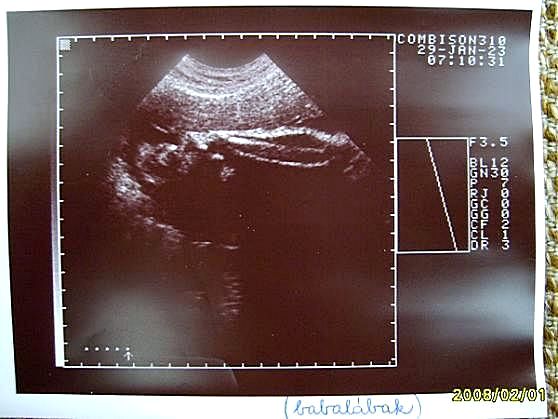

32+5 Babalábak #1 (08/01/15)